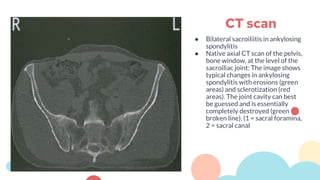

● Bilateral sacroiliitis in ankylosing

spondylitis

● Native axial CT scan of the pelvis,

bone window, at the level of the

sacroiliac joint: The image shows

typical changes in ankylosing

spondylitis with erosions (green

areas) and sclerotization (red

areas). The joint cavity can best

be guessed and is essentially

completely destroyed (green

broken line). (1 = sacral foramina,

2 = sacral canal

CT scan